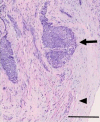

An 82-year-old woman with a history of bladder cancer presented with dyspnea and loss of consciousness. Contrast-enhanced computed tomography revealed pulmonary embolism, and emergency thrombus aspiration therapy was performed, but the thrombus was not aspirated. Echocardiography showed mobile masses in the heart and a right-to-left shunt due to a patent foramen ovale (PFO). Magnetic resonance imaging showed multiple cerebral infarctions. Surgical thrombectomy and PFO closure were performed, and the patient was diagnosed with intracardiac metastasis of bladder cancer based on intraoperative histopathology. This is a rare case of concomitant pulmonary and cerebral tumor embolism and intracardiac metastasis from bladder cancer.